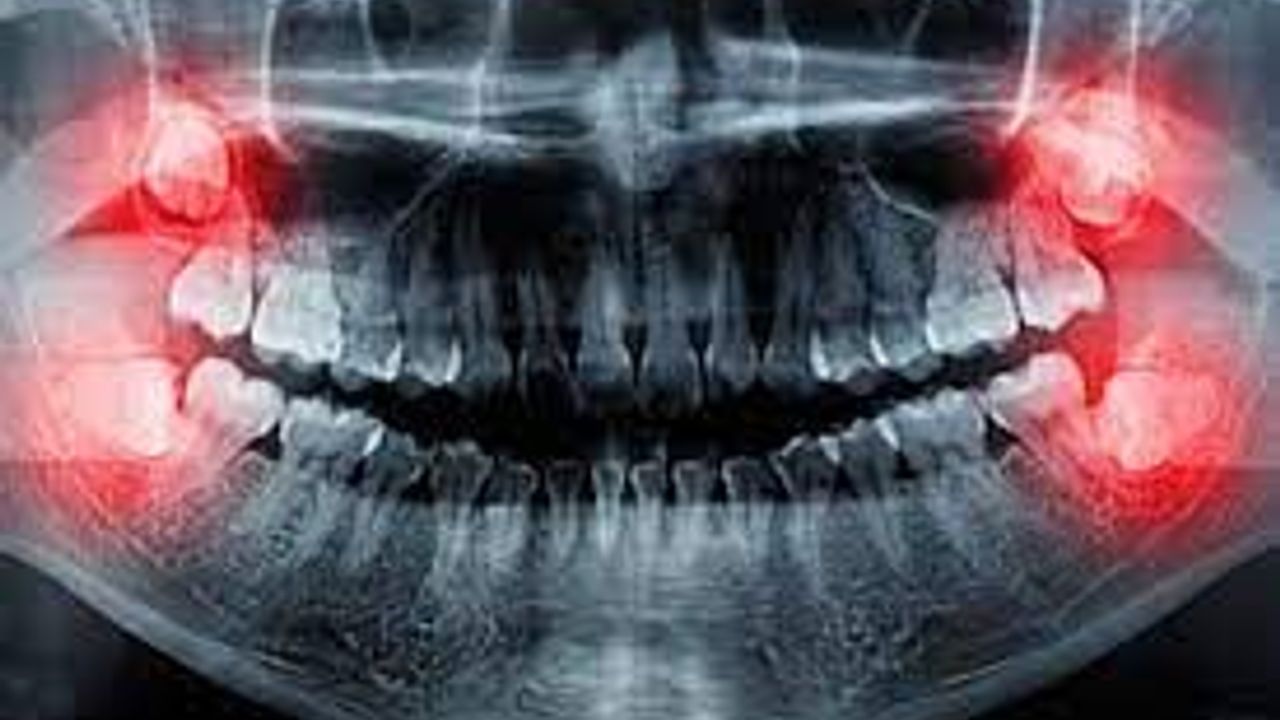

Yirmilik dişlerin herkesin hayatında bir dönüm noktası olduğunu söylemek mümkün. Bu dişler genellikle ergenlik ya da erken yetişkinlik dönemlerinde çıkmaya başlar ve birçok kişi için bir takım sorunlara yol açabilir. Yirmilik dişlerin çekilmesi gerekip gerekmediği, tedavi süreci ve çekimi sonrasında yaşanan ağrılar da bu konuyla ilgili merak edilen konular arasında yer alır. Bu haberimizde, yirmilik dişlerin ne olduğu, çekilmesi gerekip gerekmediği ve çekim süreci hakkında detaylı bilgiler bulabilirsiniz.

Yirmilik dişlerin çekilmesi, bazı durumlarda gereklilik arz edebilir. Örneğin, çıkan yirmilik dişler çevredeki dişlere baskı yaparak ağrıya neden olabilir. Ayrıca, çürük veya enfeksiyon gibi diş problemleriyle de ilişkilendirilebilir. Tedavi süreci ise yirmilik dişin durumuna bağlı olarak değişiklik gösterebilir.

Yirmilik diş ağrısı genellikle şiddetli bir şekilde hissedilir ve kişilerin günlük yaşamlarını olumsuz yönde etkileyebilir. Ağrının nedenleri arasında çıkış yolu olmadığı için diş etlerinde şişlik ve iltihaplanma oluşması, dişin çene kemik tarafından kapatılması ya da diğer dişlerle uyumsuz bir şekilde çıkması gibi durumlar yer alabilir.

Yirmilik diş çekimi işlemi, genellikle lokal anestezi altında yapılır. Diş hekimi, dişi çekmeden önce ağrısız bir şekilde uyuşturur. Ardından, diş eti ve kemik dokusu üzerinde bir kesim yaparak dişi çıkarmak için gerekli alanı açar. Eğer diş çıkarken sıkışmış veya yanlış bir şekilde çıkmışsa, cerrahi bir müdahale gerekebilir. Bu durumda diş hekimi, dişi bölerek veya keserek çıkarır.